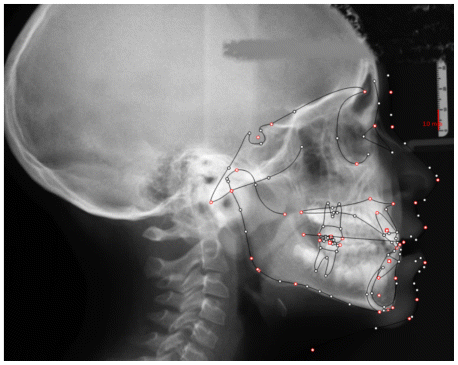

The patient was a young female presenting with a Class III dento-skeletal malocclusion, which was treated using the AMCOP® TC appliance. A comprehensive diagnostic protocol was carried out both before and after treatment, including orthopantomography (Figure 2–3), postero-anterior teleradiography (Figures 4, 5), latero-lateral cephalometric radiography (Figures 6, 7), cephalometric analysis (Tables 1, 2), as well as extraoral (Figures 8, 9) and intraoral photographs (Figures 10, 11). The extraoral examination revealed an edge-to-edge incisal relationship and the presence of a midline diastema. Pre-treatment cephalometric analysis (Deltadent® Lana, Bolzano, Italy) confirmed the diagnosis of a skeletal Class III malocclusion. The treatment plan involved the use of the AMCOP® TC appliance. The patient was instructed to wear the device for two hours in the afternoon and throughout the night for the first six months, followed by nighttime use only for an additional six months. Upon completion of the treatment, the patient achieved a Class I occlusion, with correction of both overjet and overbite. Additionally, the device facilitated tongue re-education and contributed to the postural realignment of the first cervical vertebra.

| Cephalometric Analysis before Treatment | Values (°) | Normal Values (°) |

|---|---|---|

| SNA | 81,3 | 82 ± 3 |

| SNB | 82,9 | 80 ± 3 |

| ANB | −1,6 | 2 ± 2 |

| OVJ | 3.5 | 3.5 ± 2,5 |

| OVB | 0.6 | 2 ± 2,5 |

| CoGoMe | 136,0 | 128,8 ± 4 |

| Is^Ans-Pns | 126,4 | 110 ± 6 |

| Li^GoGn | 106 | 94 ± 7 |

| Apg-Li | 3,6 | 2 ± 2 |

| Cephalometric Analysis after Treatment | Values (°) | Normal Values (°) |

| SNA | 83,0 | 82 ± 3 |

| SNB | 84,0 | 80 ± 3 |

| ANB | 1,0 | 2 ± 2 |

| OVJ | 2,5 | 3.5 ± 2,5 |

| OVB | 1,5 | 2 ± 2,5 |

| CoGoMe | 128,0 | 128,8 ± 4 |

| Is^Ans-Pns | 115,4 | 110 ± 6 |

| Li^GoGn | 99,7 | 94 ± 7 |

| Apg-Li | 2,0 | 2 ± 2 |